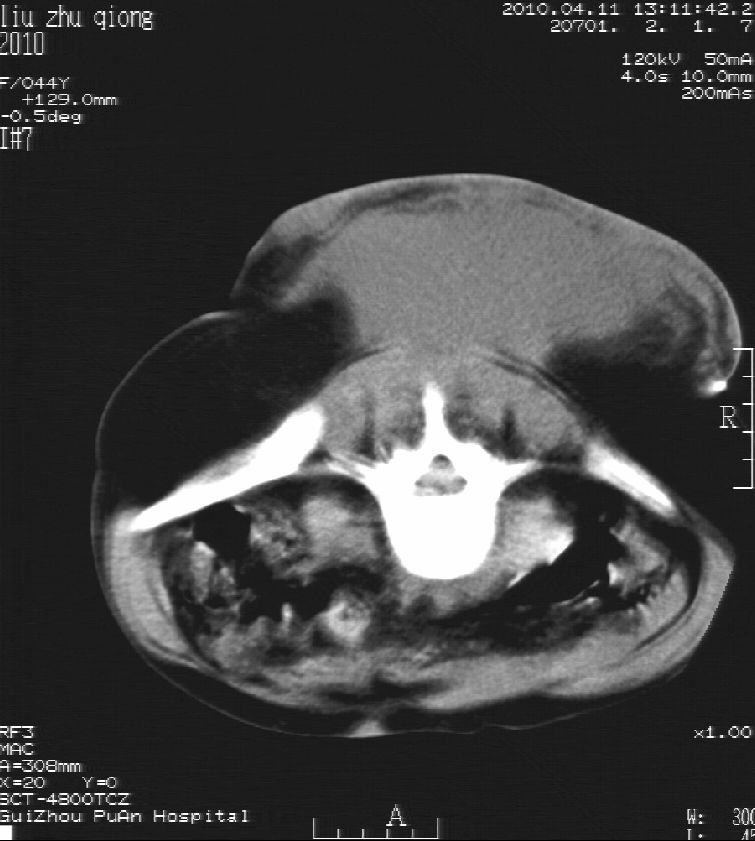

刘某,女,44岁,生第一胎时发现腰背部肿块,黄豆大小,至今17年,呈逐年增大,现行ct检查如下,敬请各位指点。

病史:女,44岁,腰背部肿块,黄豆大小,17年,呈逐年增大。

ct示:骶骨见软组织密度影,似见细条状,或花边状高密度影,考虑不典型钙化灶,向后生长,超出皮肤,可见骶骨破坏,第5幅ct图似与骶管相通。

诊断:脊索瘤

病程长,生长慢,肿块巨大,考虑神经纤维瘤,脂肪密度可以用肿瘤生长过程中包裹入皮下脂肪解释。